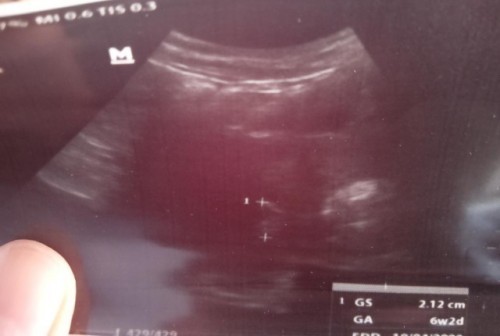

Kemarin saya usg ke dokter usia menurut usg 6w2d , menurut TAP 7w3d , Pas usg kata dokter blm pembesaran rahim tp setelah di lihat lagi kata dokter ada di sebelah kiri tapi samar samar banget, Katanya ukuran 2,12cm.. Apakah normal bun? Atau saya harus pindah dokter atau saya usg lagi kapan sebaiknya bun? Tolong jgn d bully, ini kehamilan saya yg pertama jd masih awam bun .. Makasih Oh iya saya hpht 5 juli 2021 bun, saya tespek sblm dpt haid bln agustus. ,iseng iseng TP trnyata garis dua.. #bantusharing #pleasehelp #seriusnanya